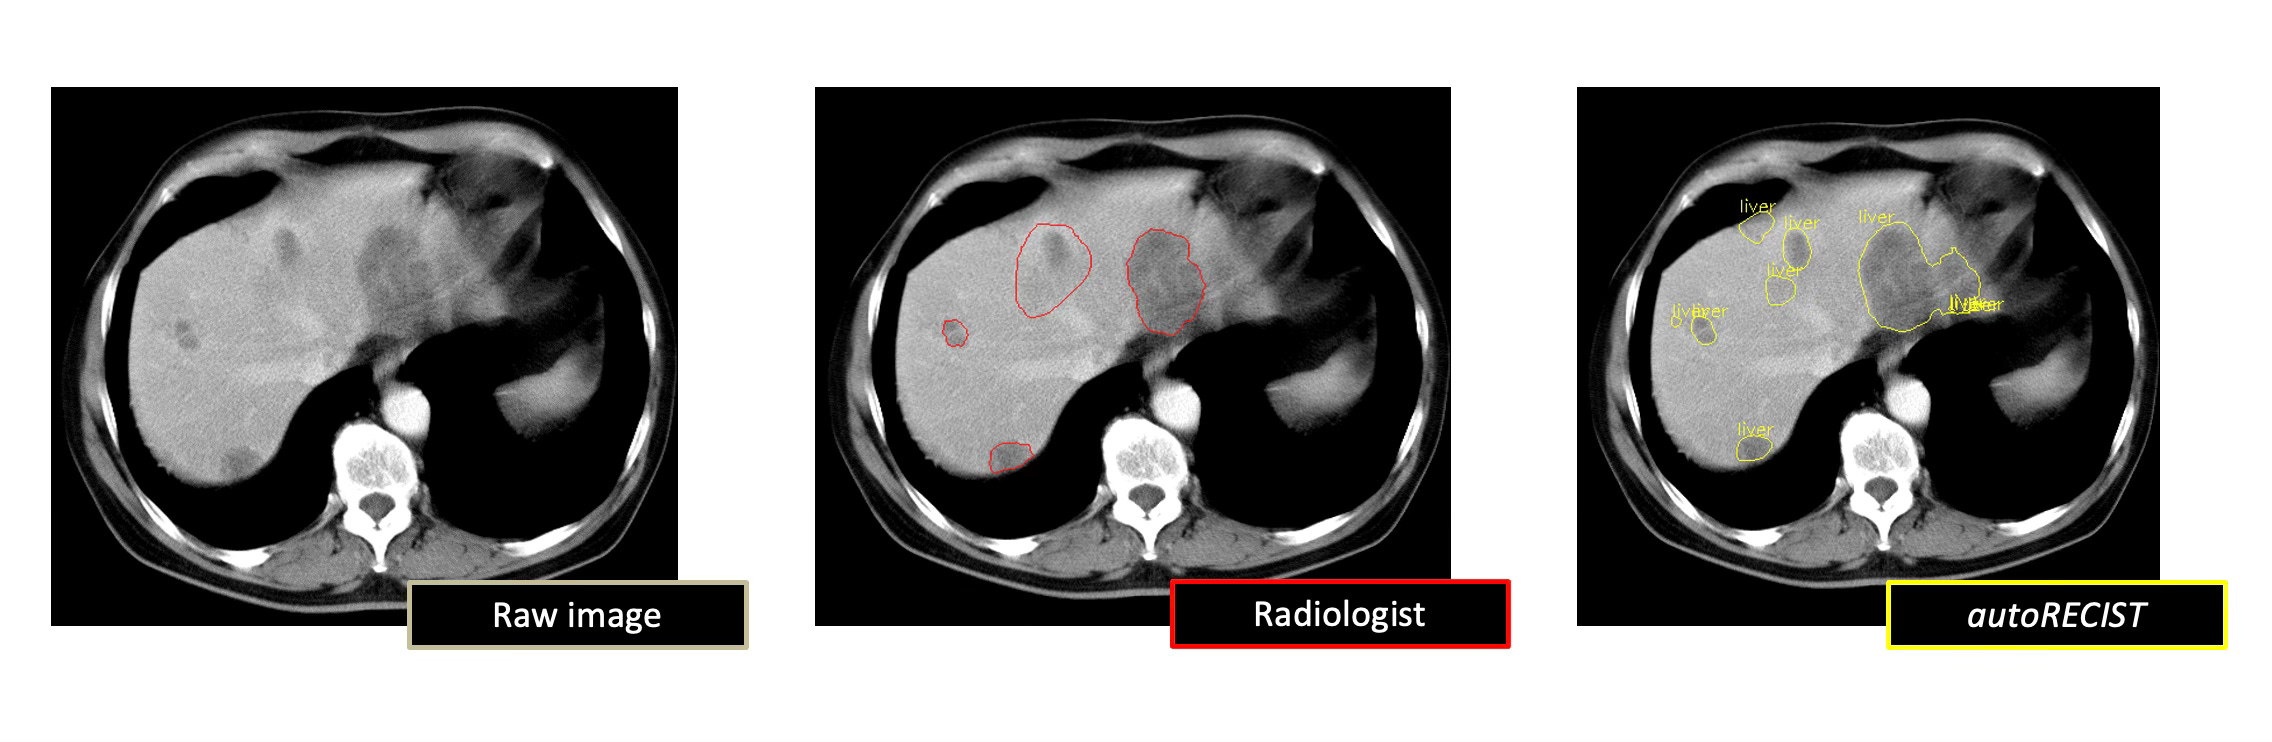

The autoRECIST initiative aims to transform the assessment of tumor burden and treatment response evaluation in oncology clinical trials by leveraging advanced AI techniques. The project focuses on developing deep learning algorithms to automate the Response Evaluation Criteria in Solid Tumors (RECIST) assessment process, which has the potential to significantly improve the accuracy, consistency, and efficiency of tumor response assessments. By automating RECIST calculations, the initiative seeks to address the limitations of manual tumor assessment driven by human visual inspection, such as the 30% discordance in radiological evaluation of tumor-based endpoints between primary investigator and independent radiologist reviews in registrational studies. Furthermore, Project Data Sphere aims to build upon the foundation of autoRECIST to develop autonomous AI agents for the evaluation of tumor burden and dynamics based on DICOM imaging, which can provide a more comprehensive and nuanced assessment of tumor response to treatment.